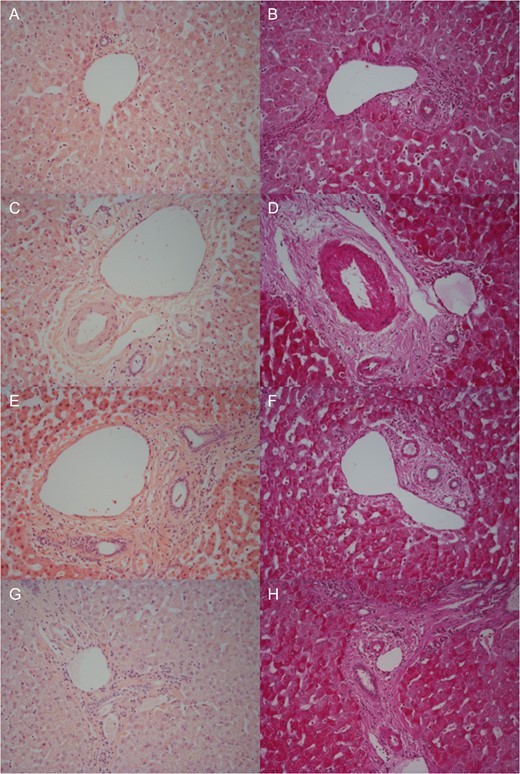

Moderate sinusoidal vasodilatation was noted throughout although milder post-splitting (Fig. 4A, C, E and G). There were no necrotic hepatocytes post-splitting (Fig. 4G). Macrovesicular steatosis was low (< 10%) pre-NMP-L (Fig. 4A) and remained unchanged (Fig. 4G). There was no intrahepatic bile duct injury. The trend was for increasing PAS staining over time (Fig. 4B, D, F and H).

Representative histological samples to assess architectural integrity and necrosis by H&E staining (A, C, E, G) as well as glycogen content using Periodic acid-Schiff staining (B, D, F, H). Samples taken prior to commencement of NMP-L (A, B), after 3 h of NMP-L (C, D), after 6 h of NMP-L (E, F) and after parenchymal splitting with concurrent NMP-L (G, H).